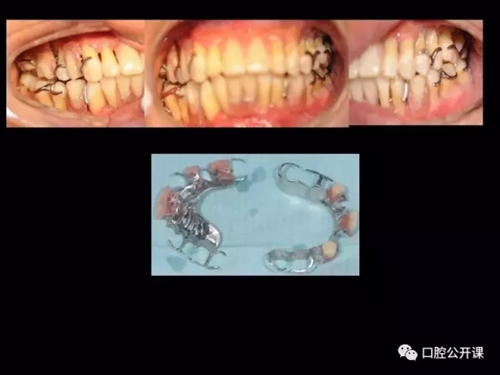

一例廣泛型侵襲性牙周炎5年臨床追蹤下

楊淑銀醫(yī)師用他的一例侵襲性牙周炎五年臨床病例追蹤來(lái)縮影一個(gè)青年牙周醫(yī)師的成長(zhǎng)之路,帶我們一起探索看似平凡枯燥的牙周基礎(chǔ)治療到底有怎樣的重要性?